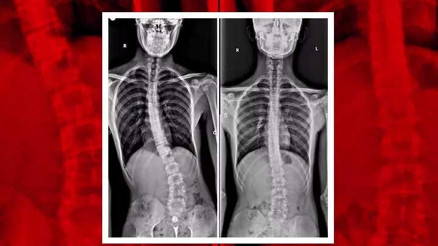

#Michael BallackSakarya’nın Adapazarı ilçesinde yaşayan 16 yaşındaki Aziz Koray Diş, geçirdiği bisiklet kazası sonrası vücudundaki eğriliğin arttığını fark edince durumu ailesiyle paylaştı. Birçok özel hastane gezen ancak teşhis konulamayan genç, tam umudunu kaybetmişken sağlığına Sakarya Eğitim ve Araştırma Hastanesi'nde kavuştu.

#SakaryaSakarya’nın Adapazarı ilçesinde yaşayan 16 yaşındaki Aziz Koray Diş, geçirdiği bisiklet kazası sonrası vücudundaki eğriliğin arttığını fark edince durumu ailesiyle paylaştı. Birçok özel hastane gezen ancak teşhis konulamayan genç, tam umudunu kaybetmişken sağlığına Sakarya Eğitim ve Araştırma Hastanesi'nde kavuştu.